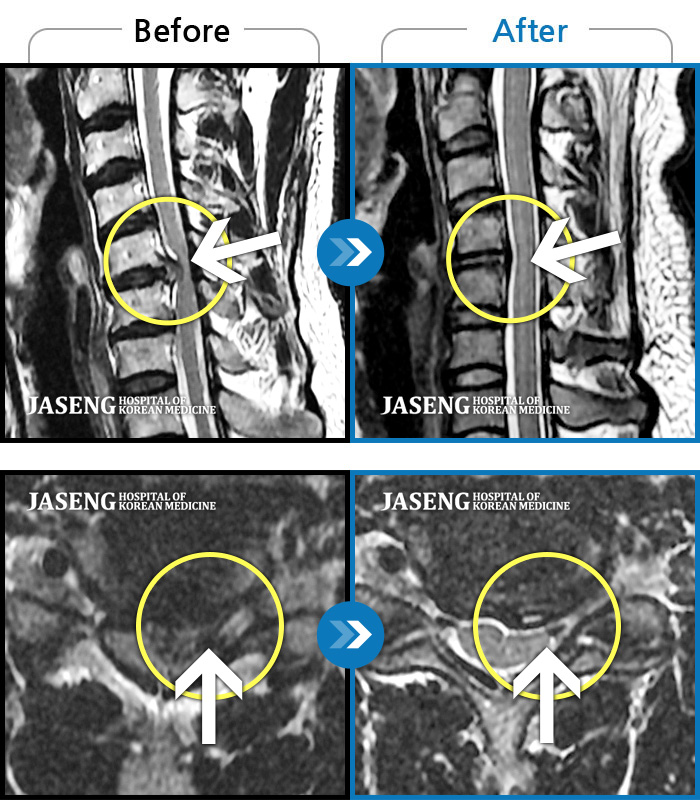

목디스크

부천 · 최요섭 원장

자고 일어난 후 발생한 극심한 후경부 통증 및 좌측 상완부의 저림

촬영시기

2024.01.11 ~ 2024.07.20

2024.07.26